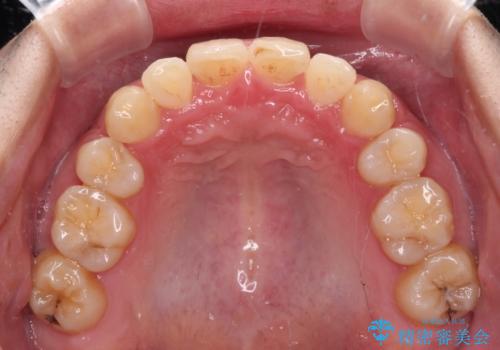

強い咬み込みですり減った前歯 デコボコを抜歯矯正で整える

口元の突出感はないものの、上顎前歯のデコボコが著しかったため、上顎左右第一小臼歯2本を抜歯することとしました。

咬合力が非常に強く、抜歯したスペースがなかなか閉じないであろうことは予想できましたが、思っていた以上に期間がかかりました。

前歯のすり減りも著しかったため、仕上げの位置の調整にも期間を要しました。